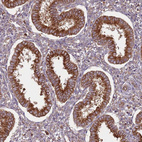

Immunohistochemical staining of human kidney shows strong cytoplasmic positivity in cells in tubules.